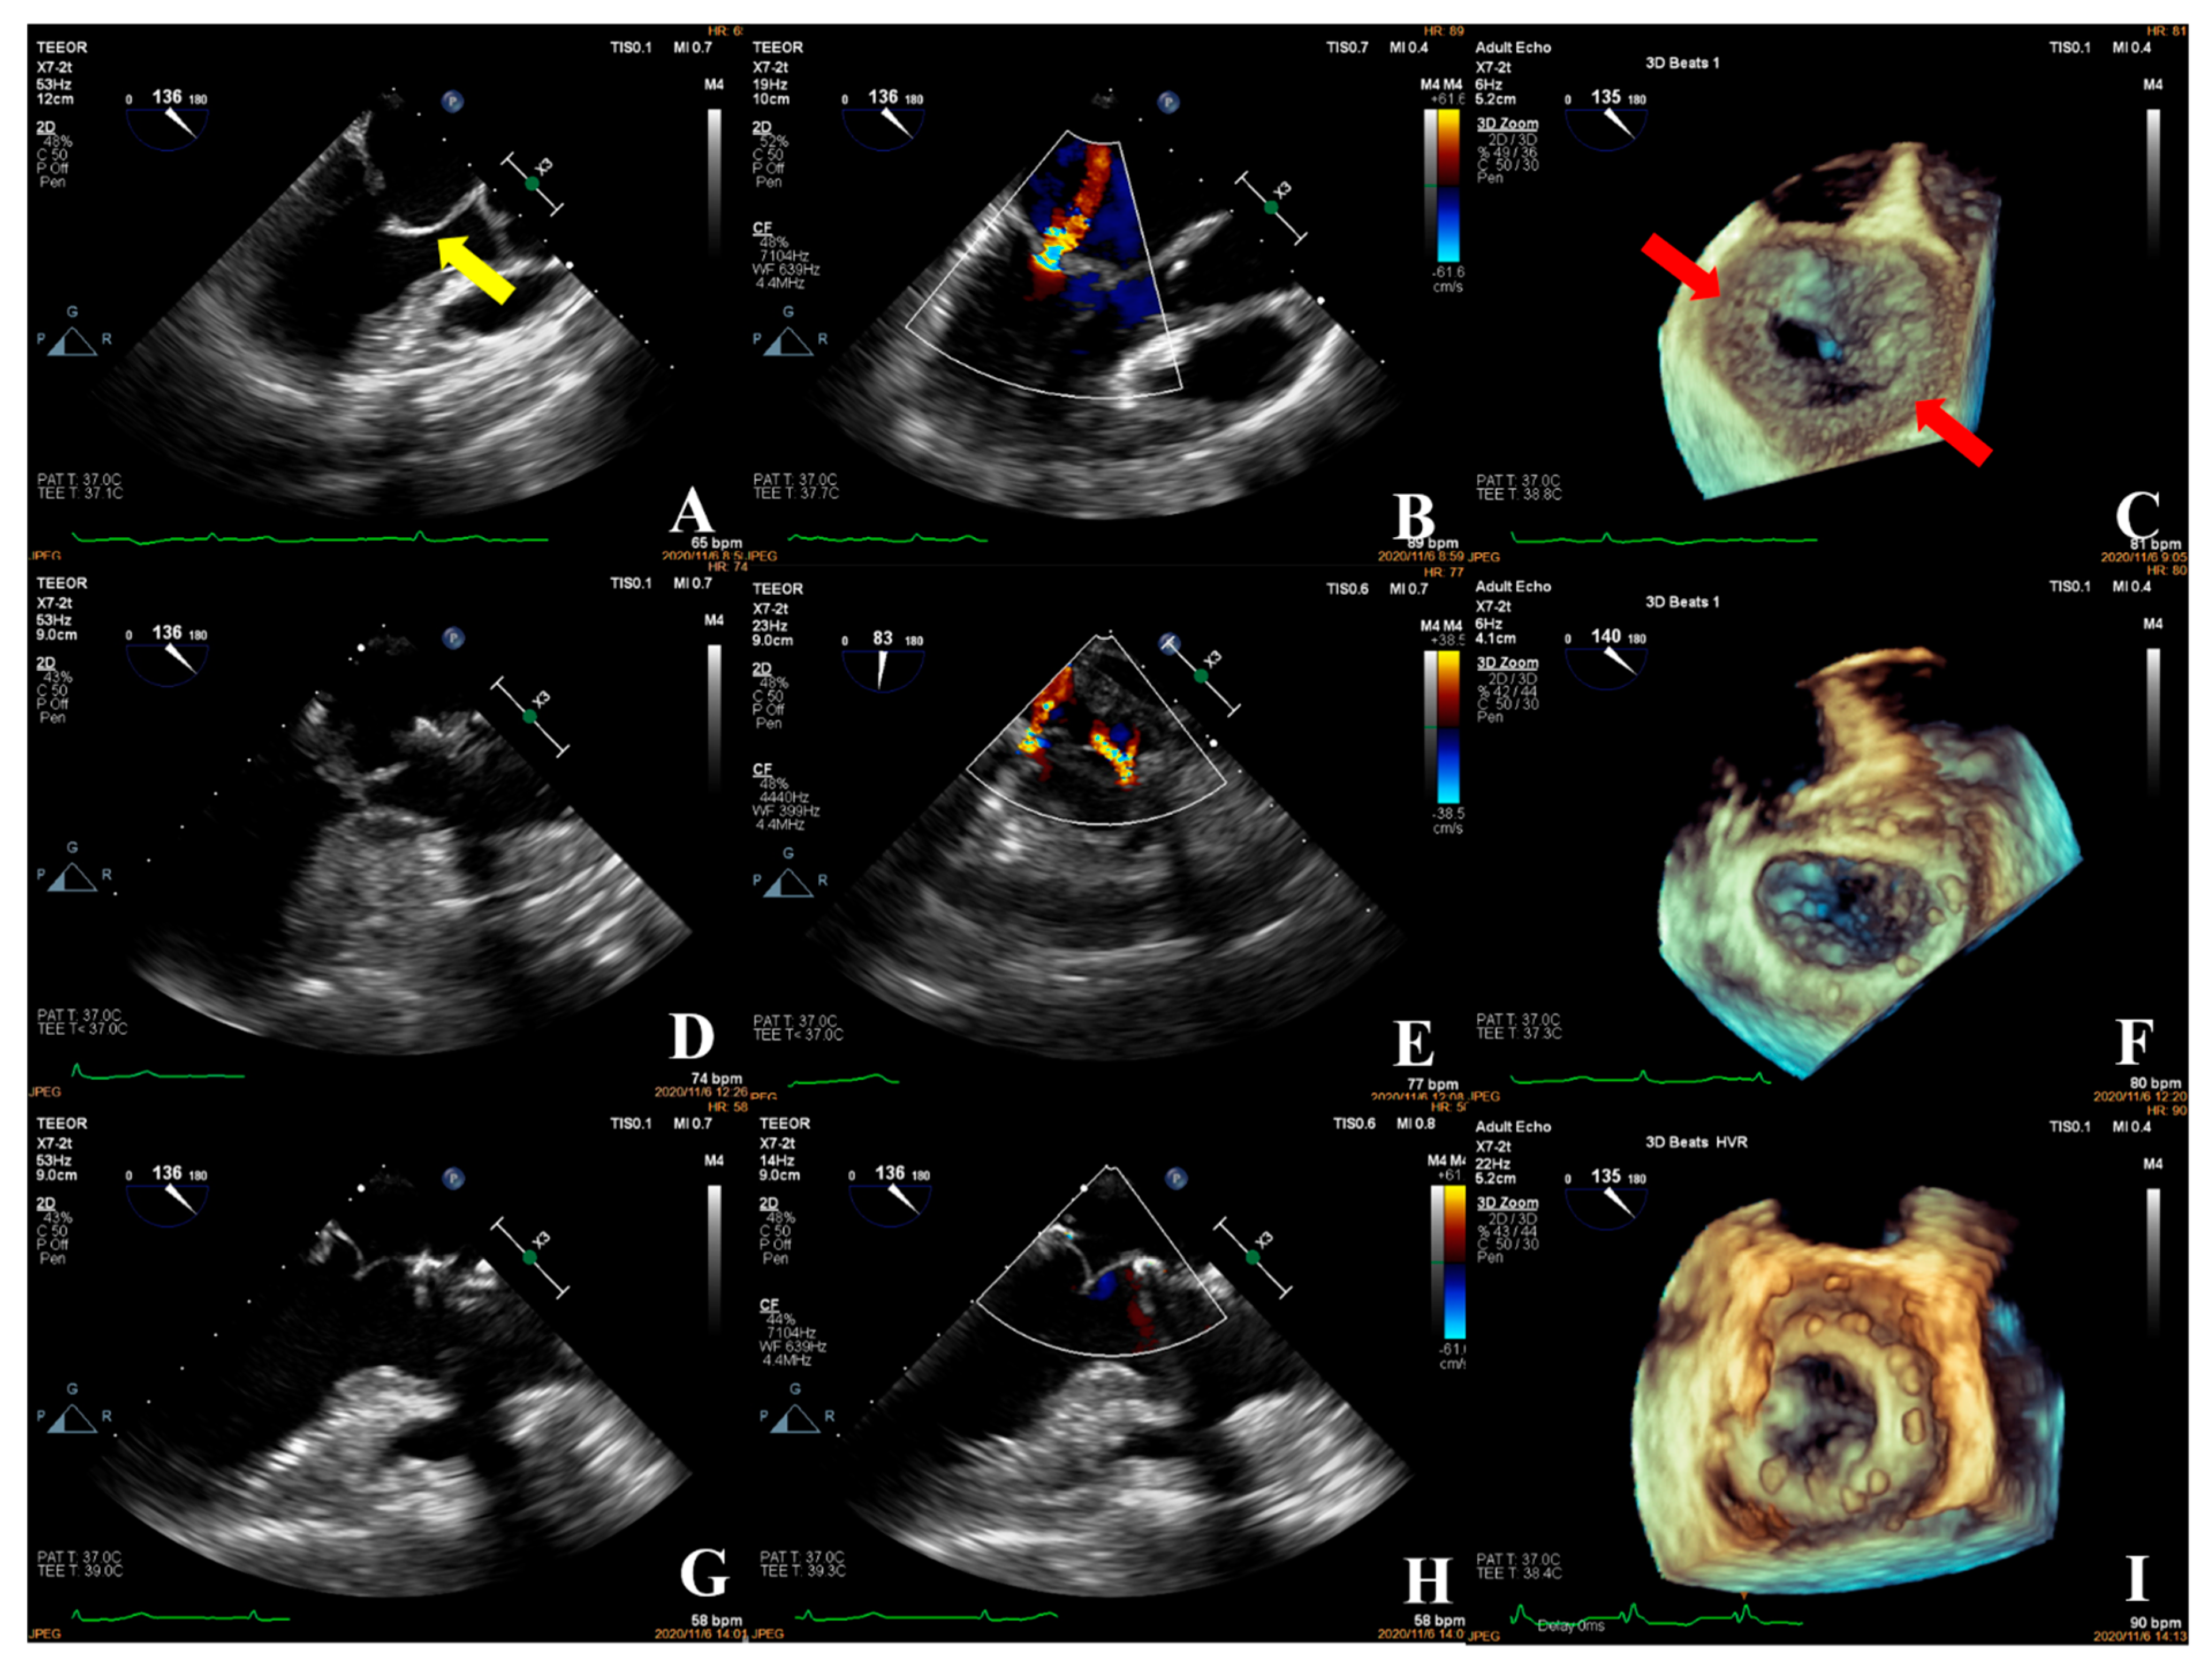

- The fourth case was an unsuccessful mitral valve repair that was converted to mitral valve replacement (Figure 10). The patient had rheumatic valvular disease, with thickened leaflets, restricted leaflet mobility, thickened and shortened sub-valvular chordae tendineae, and commissural fusion observed on three-dimensional images. The complexity score was 8 (1 + 3 + 2 + 2). According to the surgeon’s experience, mitral valve repair was expected to be performed, but the surgical effect was not satisfactory and the patient required a second bypass run. After resuscitation, the intraoperative TEE examination showed that the function of the artificial valve was good.